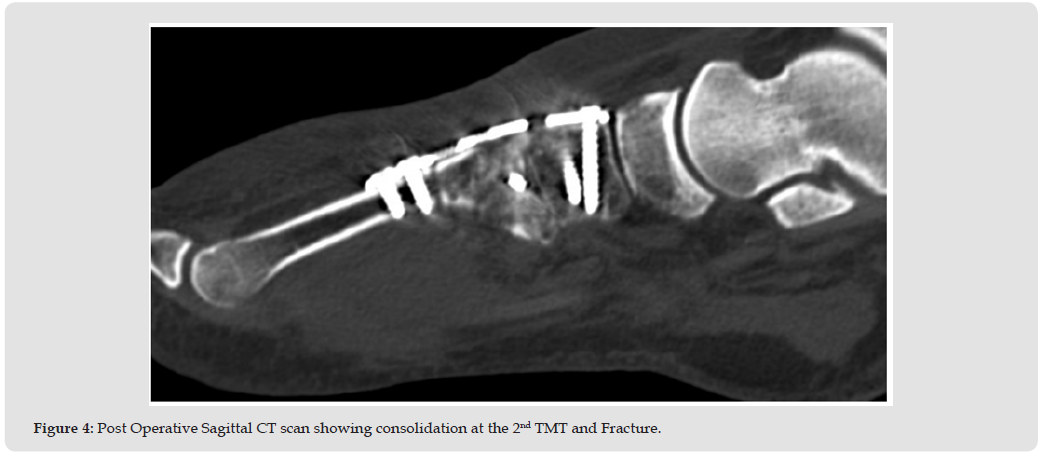

The patient is a 34-year-old morbidly obese female (height 65 in, weight 372 lbs., BMI-61) presenting with disabling right foot pain resulting from a fall (stumbling while stepping down off a porch), where she was taken to the ER and received pain medication which the patient claimed did not provide adequate relief. The surgeon saw her the following day, and X-rays showed a comminuted fracture of the second metatarsal base with intra-articular involvement and slight malalignment of the medial cuneiform with the first metatarsal base. There were also comminuted fractures involving the medial cuneiform, lateral cuneiform, and the cuboid bones, consistent with Lisfranc fracture. Other than morbid obesity, the patient history did not reveal any other significant co-morbidities. The risks and benefits of the surgery and length of recovery were discussed at length with the patient and the surgery was scheduled. The surgery consisted of TMT fusion of the first, second, and third TMTJ, and open reduction and internal fixation (ORIF) of the cuboid bone. At all times during the surgery particular care was used to avoid any damage to neurovascular structures. The first TMTJ was prepared by distraction and fenestration to allow for the placement of Catalyst Bone Graft substitute to promote fusion at the site and a Paragon 28 Lisfranc plate (Zimmer Biomet, Warsaw, IN) was inserted over the fusion site with both locking and non-locking screws.

The position and correct placement of the construct was confirmed using fluoroscopy. The second TMTJ joint was prepared using a separate incision however the second metatarsal base was in severe comminution and required a cannulated “home run” screw (provides axial compression across a joint) from the second metatarsal to the medial cuneiform. The medial and intermediate cuneiform surface was prepped for fusion and both Catalyst bone graft and a Paragon 28 Lisfranc plate were again used to secure the construct. The third TMTJ was similarly prepared with Catalyst used to promote fusion at the site. In this case a Paragon 15mm staple was used to complete the construct with adequate compression. The first and second TMTJ fusions were performed through separate incisions with the third using the same incision as the second. A separate incision was made for the ORIF of the cuboid bone where any hematoma or unwanted debris were cleared, the fracture was then reduced and held temporarily with a K-wire until a Paragon 28 cuboid fracture plate was placed on the dorsal aspect of the cuboid and accompanying screws were placed using standard lag technique. Intraoperative fluoroscopy showed adequate reduction and proper placement of all internal fixation. Both deep and subcutaneous wounds were closed, and the patient tolerated the procedure well. The procedure took approximately 3 hours with blood loss of only 100 ml.

After a brief period in PACU the patient was discharged from the hospital and returned home. The patient was followed closely post-operatively. Pain, swelling, and ROM continuously improved at each visit while the patient was NWB. At the two-month follow-up some early consolidation of the bone graft was observed at the TMTJ grafted sites as evidenced on X-ray, with no pain following ROM of the mid-tarsal joint. At this point, the patient was instructed to begin partial weight bearing with her boot and a walker. Narcotic pain medication was no longer needed by the patient and discontinued by 10 weeks. At 12 weeks a CT scan showed bony bridging at the arthrodesis sites along with appropriate reduction of the Lisfranc complex. At 14 weeks the patient had transitioned to weight bearing in a regular shoe and reports no pain on physical examination. From this point the patient will return for follow-up only if needed.

Early bone graft consolidation was noted in this patient as early as 8 weeks post-operatively and was complete as evidenced on CT scan by 12 weeks. The early graft consolidation in this case is both interesting and encouraging. This case sets the stage for further research with long term follow-up using Catalyst Bone Graft for any foot and ankle procedure where bone graft is required for predictable and rapid healing (Figures 1-5).